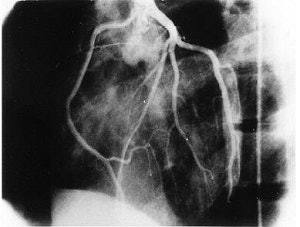

![]() |

| The same 17-year-old asymptomatic basketball player. Coronary artery angiography in the left oblique anterior view. Selective injection of contrast medium in the left sinus of the Valsalva confirms that the right coronary artery originates from the left sinus just anterior to the left coronary ostium. Zeppilli P, dello Russo A, Santini C, Palmieri V, Natale L, Giordano A, Frustaci A, "In vivo detection of coronary artery anomalies in asymptomatic athletes by echocardiographic screening" (Chest, 1998 Jul;114(1):89-93). |